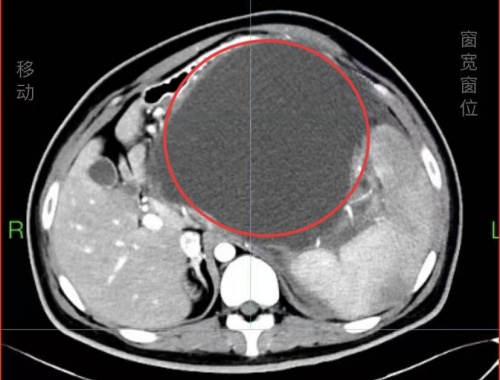

CT影像下的巨大囊肿。

长沙22岁的小伙子小张最近一段时间腹部逐渐隆起,仿佛怀胎数月,还伴有上腹胀痛、恶心呕吐等症状,到捷克论坛 消化内科就诊,医生发现其腹腔内长出一个直径16厘米的巨大胰腺假性囊肿,严重压迫周边脏器,犹如一枚“定时炸弹”,十分危险。捷克论坛 消化内镜中心团队运用超声内镜引导定位,精准实施内外引流术,以微创方式化解危机。

小张三个月前因凶险的急性坏死性胰腺炎在鬼门关走了一遭,在家附近医院经救治才脱离危险。没想到胰腺炎引发胰腺体尾部假性囊肿,囊肿迅速长大,几乎占据了腹腔的“半壁江山”,不仅将胃、十二指肠等重要脏器挤压变形,更随时有破裂引发感染、大出血,小张再次面临致命风险。

术中,消化内科刘鹏主任团队在超声内镜的精准定位下,将穿刺针刺入囊肿腔,抽出约80毫升囊液。随后又经胃壁向囊肿内植入2根支架,建立起囊肿与胃腔之间的内引流通道,使囊液得以持续流入消化道。同时放置1根鼻囊肿引流管进行外引流,进一步确保引流效果并便于术后冲洗。这种“双管齐下”的内外引流策略,为囊肿的彻底消退提供了双重保障。在团队紧密协作下,手术过程不足1小时,术后,小张症状缓解,于6月9日顺利出院。“还以为要开刀动大手术,没想到手术没有在孩子身体上留下伤口,出血也很少。”小张的母亲表示。